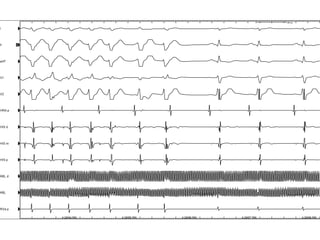

¿Medicamento responsable?

A.  Amiodarona

B.  Carvedilol

C.  Digoxina

D.  Propafenona

Amiodarona

Digoxina

Carvedilol

Propafenona

Propafenona & Flecainida

•  Disminuyen la velocidad de conducción auricular mediante

bloqueo de canales rápidos de Na+, favoreciendo la

estabilidad de circuitos de macrorreentrada.

•  Debido al enlentecimiento de la velocidad de conducción

auricular, los flutter IC suelen ser lentos, y se pueden

conducir 1:1 a los ventrículos.

•  Aberrancia en la conducción dependiente de frecuencia.

•  Deben ser usados con bloqueadores del NAV como B-

bloqueo o Ca+2 antagonistas.